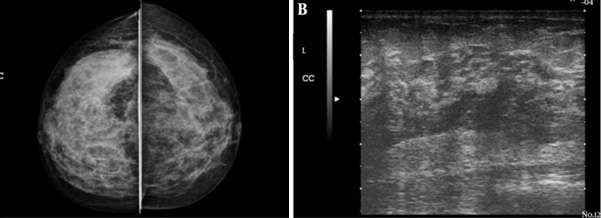

The most common complication includes breast abscess, occurring in 0.4-11% of patients with mastitis and is more frequently seen in cases of inadequately treated or late-presenting mastitis. If rupture of an abscess occurs, a resultant draining sinus and mammary fistula can occur. Diagnosis of lactational mastitis is based on clinical grounds, however ultrasound can be useful in differentiating between mastitis (ill-defined hypoechoic region) and a breast abscess (hypoechoic to anechoic mass with internal debris and surrounding vascularity) if there is a poor clinical response to antibiotics. Mammography is not usually performed but can show skin and trabecular thickening from breast edema.

Case: Mastitis Figure 1

Figure 1. Ultrasound grayscale image from Boakes et al. shows an irregular heterogeneously hypoechoic lesion with partially circumscribed and partially indistinct margins measuring up to 6.3 cm, consistent with a breast abscess.